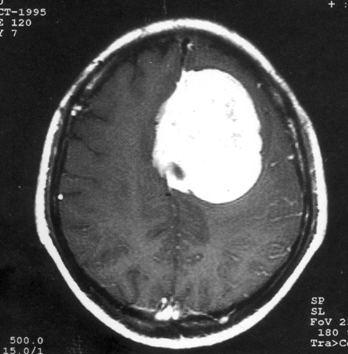

病历摘要:??患者女性,37岁。大便时突起炸裂样头痛3小时,伴喷射样呕吐。既往体健。体检:T37.5℃,BP145/90mmHg,R20次/分,P85次/...

问题 病历摘要:??患者女性,37岁。大便时突起炸裂样头痛3小时,伴喷射样呕吐。既往体健。体检:T37.5℃,BP145/90mmHg,R20次/分,P85次/分。神志清楚,颅神经检查无异常,颈强直,克、布氏征(-),四肢肌力、肌张力正常,病理征(-)。 为明确诊断,可考虑作什么检查?

选项 A.脑血管造影 B.TCD C.CTA D.MRA E.颅骨平片 F.诱发电位 G.PET H.SPECT I.脑磁图

答案 ACD